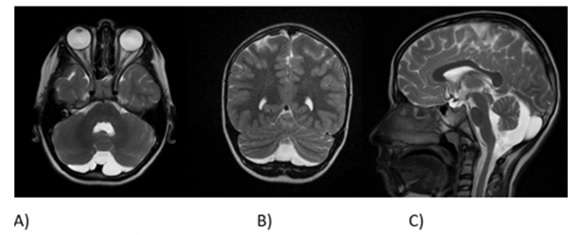

The hemoglobin electrophoresis showed that the patient’s HbF value was high; however, the results of the parents were normal (Figure 1). The patient's medical history includes an operation for an inguinal hernia. Additionally, cranial MRI imaging of the patient revealed hypoplasia in the lower cerebellar vermis (Figure 2).

The patient's medical history includes an operation for an inguinal hernia.Figure 2: The patient's medical history includes an operation for an inguinal hernia. Additionally, cranial MRI imaging of the patient revealed hypoplasia in the lower cerebellar vermis